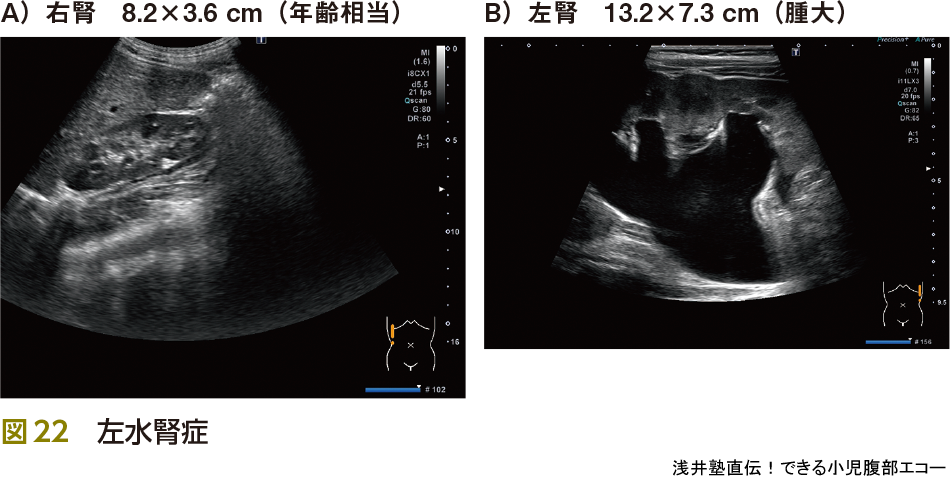

5)水腎症

水腎症は腎臓でつくられた尿の流れがせきとめられて,尿の通り道や腎臓の中に尿がたまって拡張した状態をいいます.腹痛の原因として重要です.特に腹痛の原因となるのはureteropelvic junction obstruction(UPJ:腎盂尿管移行部狭窄症狭窄)です(図22).そして原因不明のくり返す腹痛(同部位)では間欠的水腎症の発作を念頭に置く必要があります(図23).